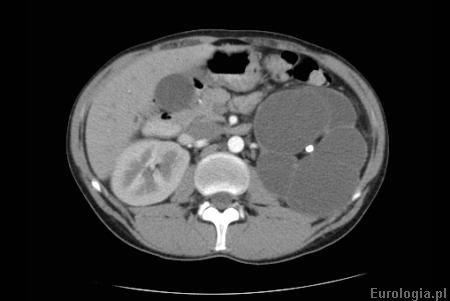

Wodonercze rozpoznawane jest na podstawie badań obrazowych. Badanie USG jamy brzusznej jest podstawowym badaniem obrazowym w diagnostyce wodonercza. W badaniu USG określany jest stopień zastoju moczu w UKM - wymiar przednio - tylny miedniczki i grubość warstwy miąższowej - kory nerki. Do obrazowania wodonercza oprócz ultrasonografii wykorzystuje się także tomografię komputerową, urografię i rezonans magnetyczny. Scyntygrafia jest badaniem, które pozwala ocenić czynność nerki. W czasie badania pacjent otrzymuje dożylnie radioaktywny znacznik a następnie ocenia się szybkość jego wydalania przez nerki.

Fot. Wodonercze lewostronne - tomografia komputerowa